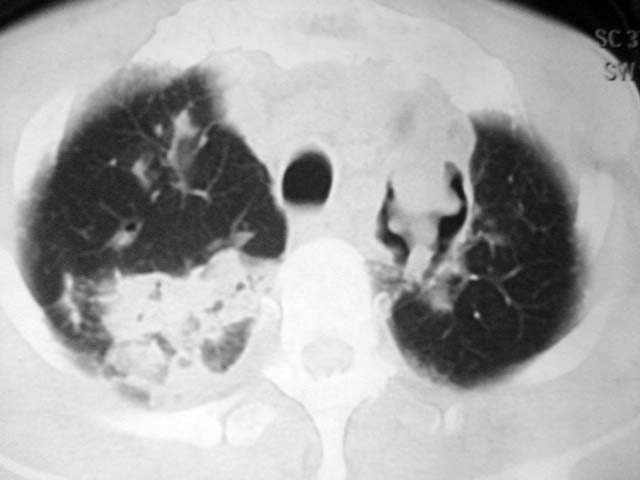

男,52岁,发热2月,糖尿病史。

抗结核治疗irpz方案,血糖未治疗,空腹15.9左右。症状无好转,左胸痛。

2、双肺见多发片状及结节状高密度影,大多数病灶中心均见“空泡征”。

3、纵隔内淋巴结肿大。

结果:两肺继发性肺结核并曲霉菌感染。